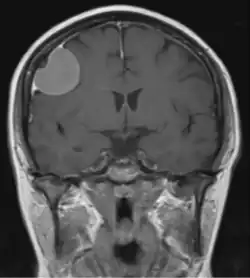

Dural tail sign

Dural tail sign seen associated with a meningioma

The dural tail sign (also known as dural thickening, the flare sign, or the meningeal sign) is a radiological finding observed in magnetic resonance imaging (MRI) studies of the brain that refers to a thickening of the dura mater immediately adjacent to a mass lesion, such as a brain tumor.[1] Initially, the dural tail sign was thought to be pathognomonic of meningioma, a slow-growing tumor that arises from the meninges.[1] However, subsequent studies have shown that it can also be observed in various intra- and extra-cranial pathologies and in spinal lesions.[1] It is not a completely sensitive finding, as it is seen in only 60-72% of cases.[2] It is not completely specific either, as it has been described associated with lesions like neuromas, chloromas, pituitary diseases, granulomatous disorders, cerebral Erdheim-Chester disease, lymphomas, metastasis, hemangiopericytomas, schwannomas, and gliomas such as glioblastoma multiforme (GBM).[2][3] The final diagnosis should be further established through cerebrospinal fluid analysis or histopathological examination following a biopsy.[3]